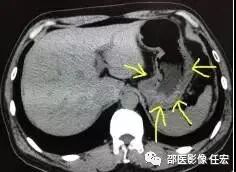

如上图1:黄色箭头指的就是胃,这是一个没有喝水,没有充盈好的胃,我们可以看到箭头指的胃壁是明显厚的,正常的胃壁也是厚的,但是如果里面隐藏长着东西,刚好胃壁这里有个小胃癌,那就没办法诊断了,就会导致漏诊。